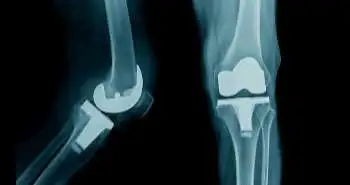

Do's and don'ts in osteoarthritis